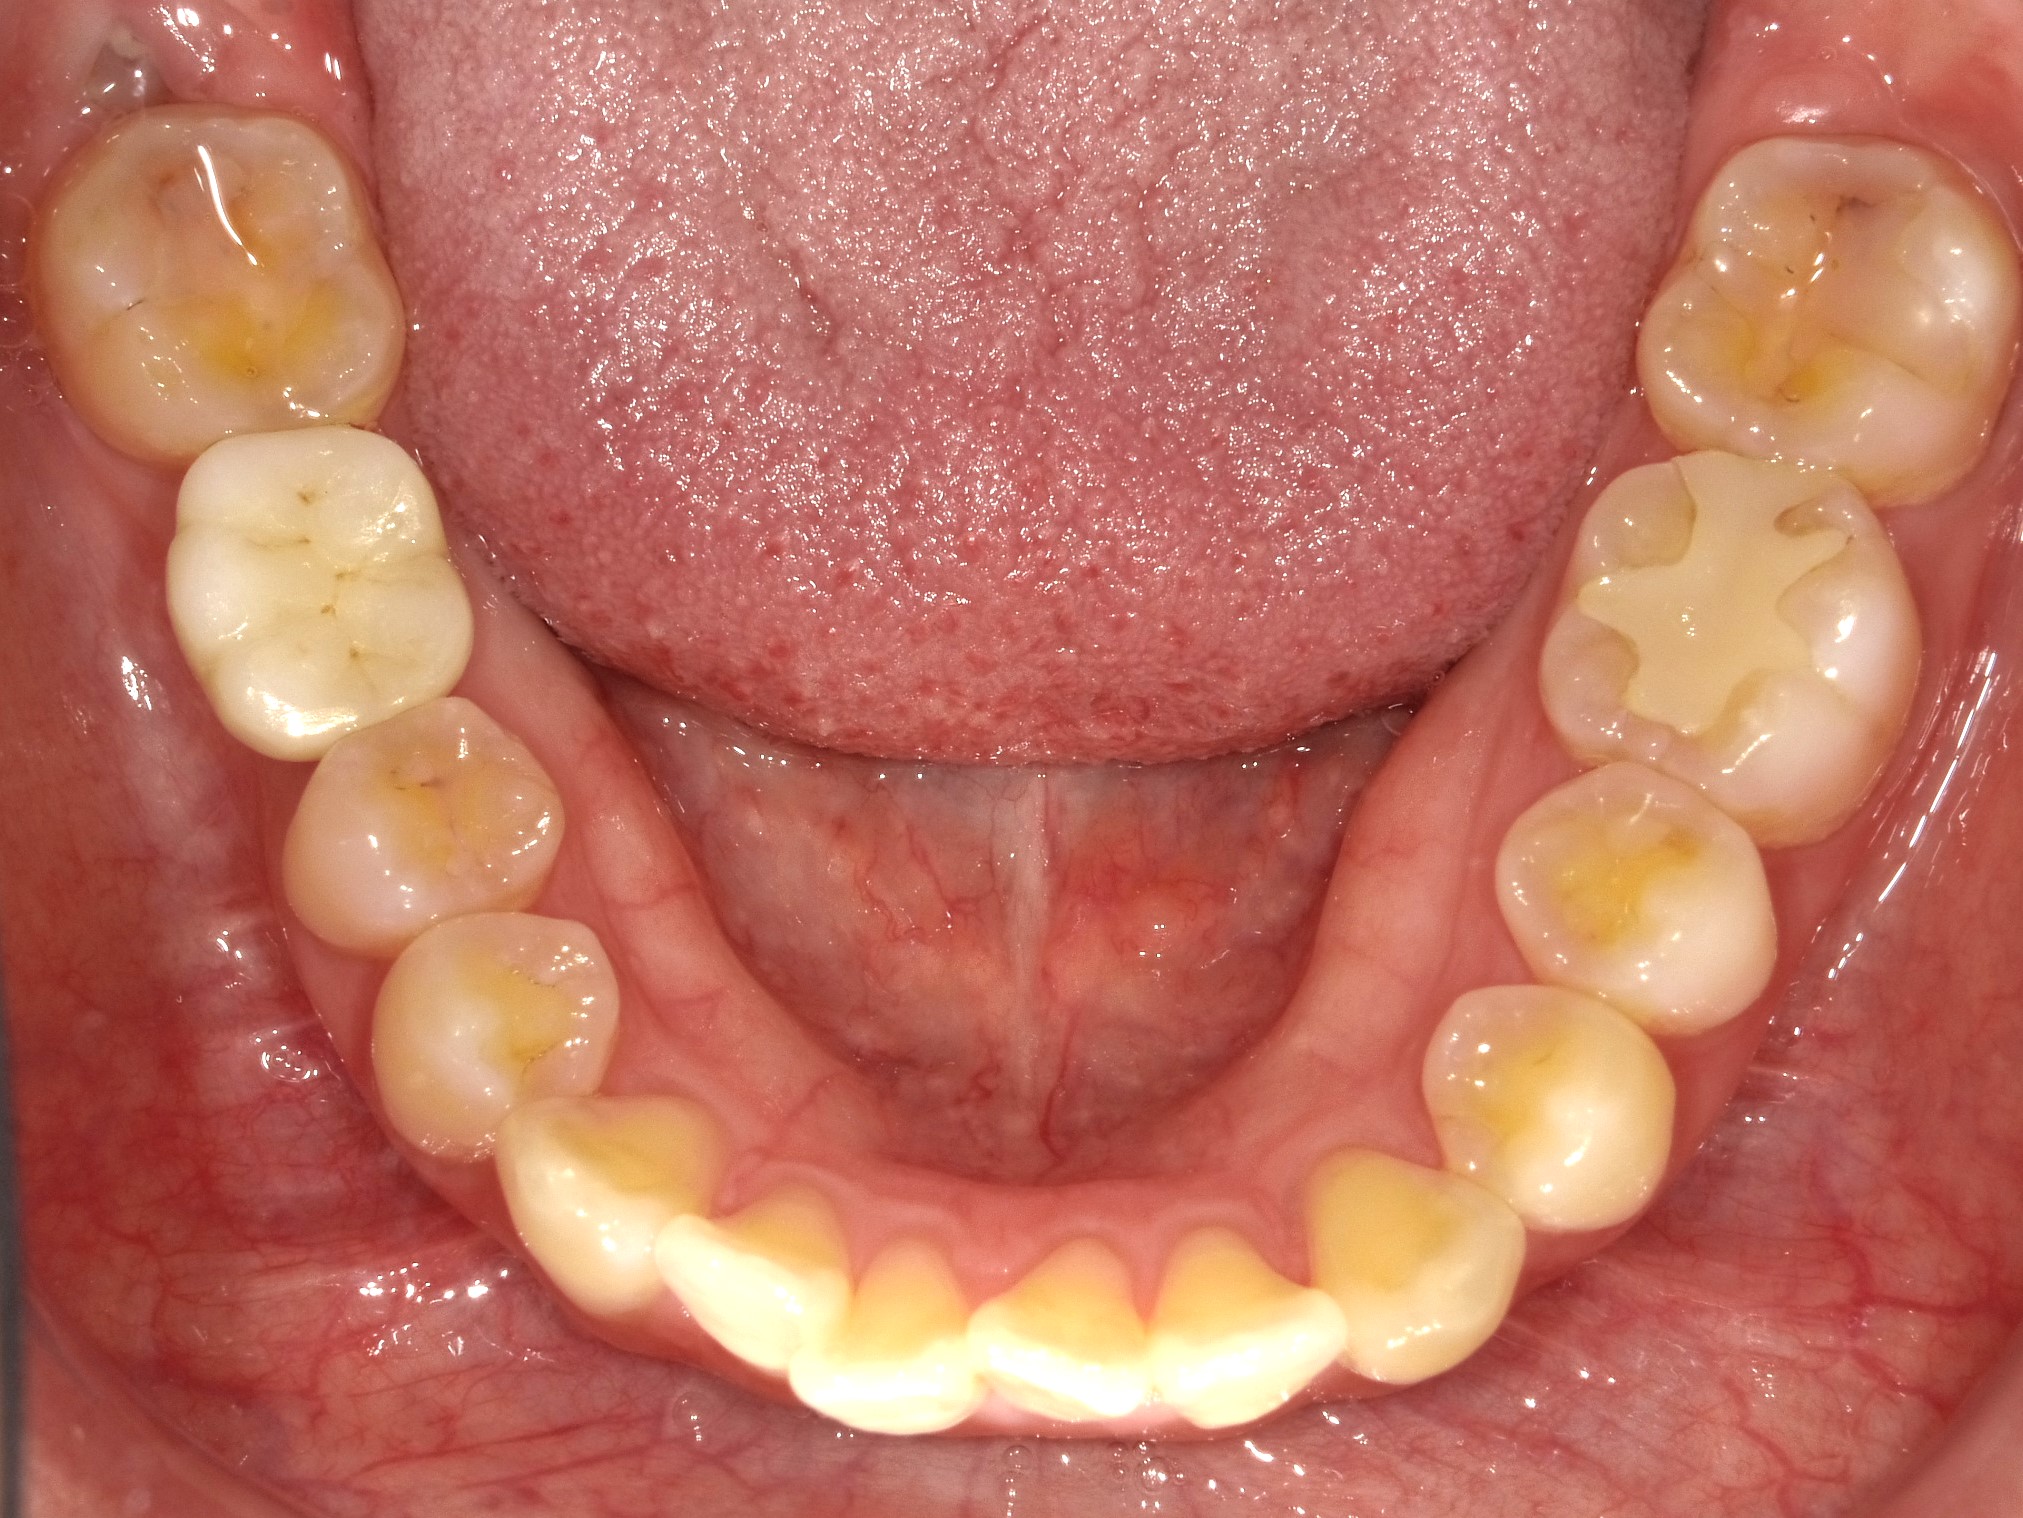

治療前